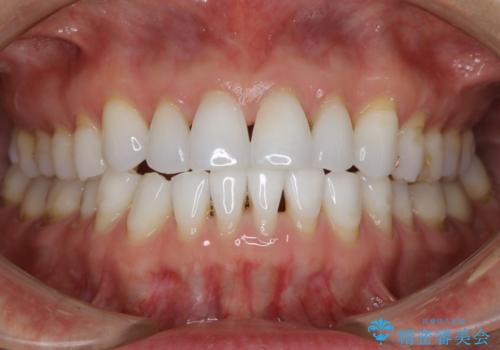

【非抜歯】インビザラインで正しい噛み合わせを

【非抜歯】インビザラインでガタつきと口元を改善!非抜歯でも印象が変わる矯正治療